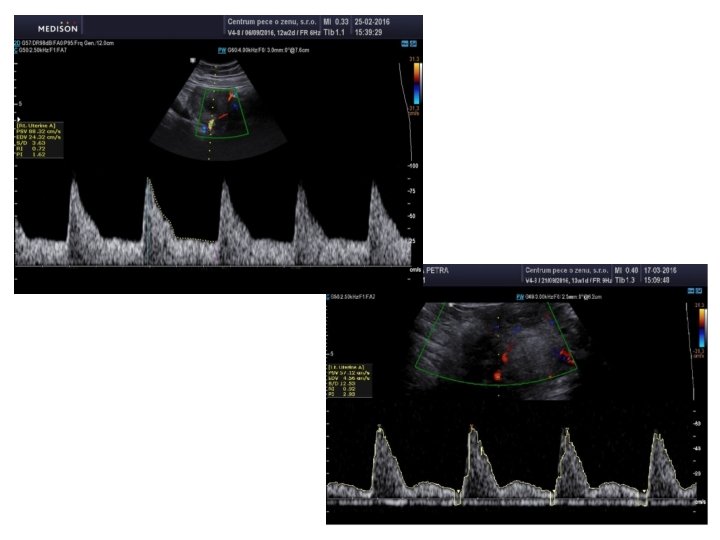

4) dopplerovské UZ měření uterinních arterií - neinvazivní metoda - nepřímé hodnocení U-P cirkulace - u preeklampsie a často i IUGR abnormální placentace rezultuje v inadekvátní U-P perfuzi, na které se podílí mimo uterinní i ovarická arterie - ABD nebo (TVS) v průběhu I. a II. , ev. III. trimestru s využitím barevného dopplerovského mapování a pulzního doppler. měření získáme charakteristické průtokové křivky

1) sagitální zobrazení děl. hrdla a DDS 2) naklonění sondy ze strany na stranu 3) barevné dopplerovské mapování 4) pulzní dopplerovské měření /PI s gatem 2 mm, úhel insonance < 30⁰, zvětšení takové, aby byl vzorkovací objem umístěn do průsvitu tepny/ 5) 3 křivky podobného tvaru na obou Ut. A, používá se nejnižší naměřená hodnota PI 6) při ABD vyšetření směruje proud krve v Ut. A v ideálním případě směrem k sondě /červeně/, max. rychlost 60 cm/s a více, tak vyloučíme záměnu za cervikální větve Ut. A

Normální nález - nízké enddiastolické toky a pokles toku v časné diastole (přítomnost zářezu, tzv. notch) - typický tvar Ut. A u netěhotných žen nebo v I. trim. - hodnoty PI Ut. A se během gravidity postupně ↓, kolem termínu porodu se mohou nepatrně ↑ - kolem 10. týdnu je normální hodnota asi 2, 5, v 16. t. t. je to 1, 5, ve 24. t. t. 1, 0, a ve 38. t. t. 0, 8 → Mo. M

Při preeklampsii - přítomnost notch v II. trim. (zejména po 24. t. t. ) asociována s inadekvátní trofoblastickou invazí - vysoká rezistence v Ut. A → abnormální tvar křivky (↑ PI Ut. A, přítomnost notch) - metaanalýza 74 studií → abnormální UZ nález v I. a zejména ve II. trim. je považován za vhodný screeningový test závážnosti a progrese PE i IUGR, přítomnost notch v Ut. A v III. trim. po 28. t. t. riziko pozdní PE - senzitivita 80 -90%, specificita 39 -47%